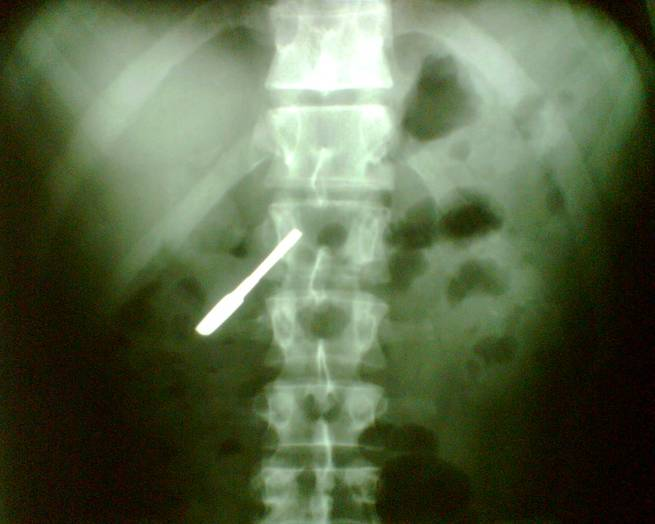

With plain radiography radiopaque foreign objects could be identified. Let’s not forget that images always should be taken at least from two directions. Plain radiographs contain summation images of one projection in order to be able to localize the object orthogonal projections are necessary, fluoroscopy and CT can also be helpful in undetermined cases.

12 A young dancer was partying in the dressing room with his friends. He suddenly swallowed down an object which on the abdominal radiogram proved to be a cupboard key.